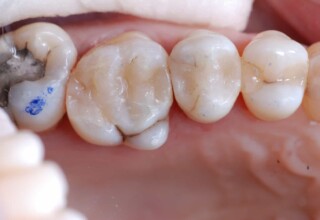

Αποκατάσταση Ραγισμένου Γομφίου με σφράγισμα Σύνθετης Ρητίνης

Τα ραγισμένα δόντια αποτελούν μια πρόκληση για την επανορθωτική οδοντιατρική από την άποψη της δυσκολίας της αποκατάστασης(συνήθως μεγάλα σφραγίσματα) άλλα κυρίως από τα προληπτικά μετρά που πρέπει να παρθούν για να αποφευχθεί ένα πλήρες κάταγμα. Η ακόλουθη περίπτωση παρουσιάζει την απλούστερη προσέγγιση της άμεσης συγκολλούμενης αποκατάστασης από σύνθετη ρητίνη. Βασίζεται στο σκεπτικό ενός συγκολούμμενου σφραγίσματος που «κρατάει» τα εναπομείναντα οδοντικά τμήματα «ενωμένα». Ο συγκεκριμένος γομφίος παρέμεινε ακέραιος για δυο χρονιά, οπότε χρειάστηκε απονεύρωση γιατί νεκρώθηκε και κατόπιν τοποθετήθηκε στεφάνη για αυξημένη προστασία.